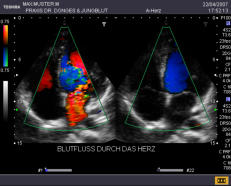

EKG Im Ruhe-EKG sehen wir Herzrhythmusstörungen, abgelaufene Infarkte oder Entzündungen des Herzmuskels. Belastungs-EKG Hier bekommen wir Hinweise auf Ihre körperliche Leistungsfähigkeit und können die Durchblutung der Herzkranzgefäße besser als im Ruhe-EKG beurteilen. Bei verengten Kranzgefäßen zeigt sich oft eine spezielle EKG-Veränderung während der Belastung, ein Herzdruck und/oder Luftnot. Herzultraschall Hier können wir genau die Pumpkraft Ihres Herzens und die Funktion der Herzklappen untersuchen, wir erkennen Infarktnarben, Klappenkrankheiten, Gerinnsel und Gewächse. Der Blutfluss durch die Herzkammern und Klappen kann mit speziellen Verfahren sicht- und hörbar gemacht werden (Farbdoppler). In die Kranzgefäße selbst können wir nicht sehen, aber aus der Beurteilung der Pumpfunktion wichtige Hinweise auf die Durchblutung erhalten. Eine exakte Aussage zu Verengungen der Herzkranzgefäße kann bei entsprechenden Hinweisen aus den Untersuchungen mit einem Herzkatheter getroffen werden. Halsschlagader-Messung Mit unseren hochempfindlichen Geräten können wir den Innendurchmesser der Halsschlagader (Carotis) genau ausmessen. Als Frühzeichen einer beginnenden Aderverkalkung nimmt diese sogenannte Intima-Media Dicke über das Altersmaß hinaus zu. Hieraus ergeben sich wichtige Konsequenzen, so z. B. die Beantwortung der Frage, ob ein erhöhter Cholesterinspiegel schon medikamentös behandelt werden muss.